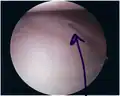

Bankart lesion seen at arthroscopy -